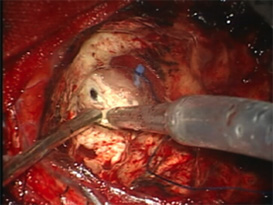

3.蛍光診断(光線診断) PhotoDiagnosis(PD)

脳腫瘍、特に神経膠腫(glioma)では摘出術中に正常の脳組織との区別が難しいことがしばしばあります。そのような場合には、脳腫瘍かと思って切除したら大事な正常脳組織であったり、また正常組織かと思われた部分が脳腫瘍の一部であるということが術後のMRI検査でわかるということもあります。これを防ぐために用いられる方法が蛍光診断です。

手術前にアミノレブリン酸というお薬をブドウ糖に溶かして内服して頂きます。そして手術中に脳腫瘍のあたりに青い光を当てると腫瘍だけが赤く光って見えます。

(左図)腫瘍を摘出後

(右図)青い光を当て、残存腫瘍だけが赤く光る。

この赤く光った部分を摘出すれば腫瘍の全摘出が完了します。